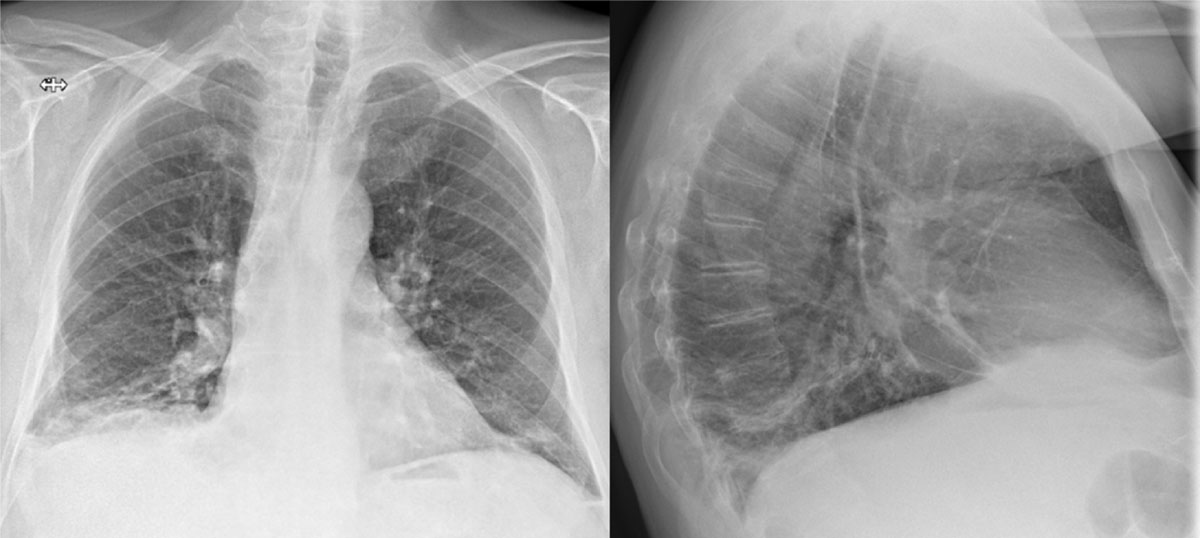

Figure 1

CXR with increased pleural fluid at the right lung basis and several dense strands.